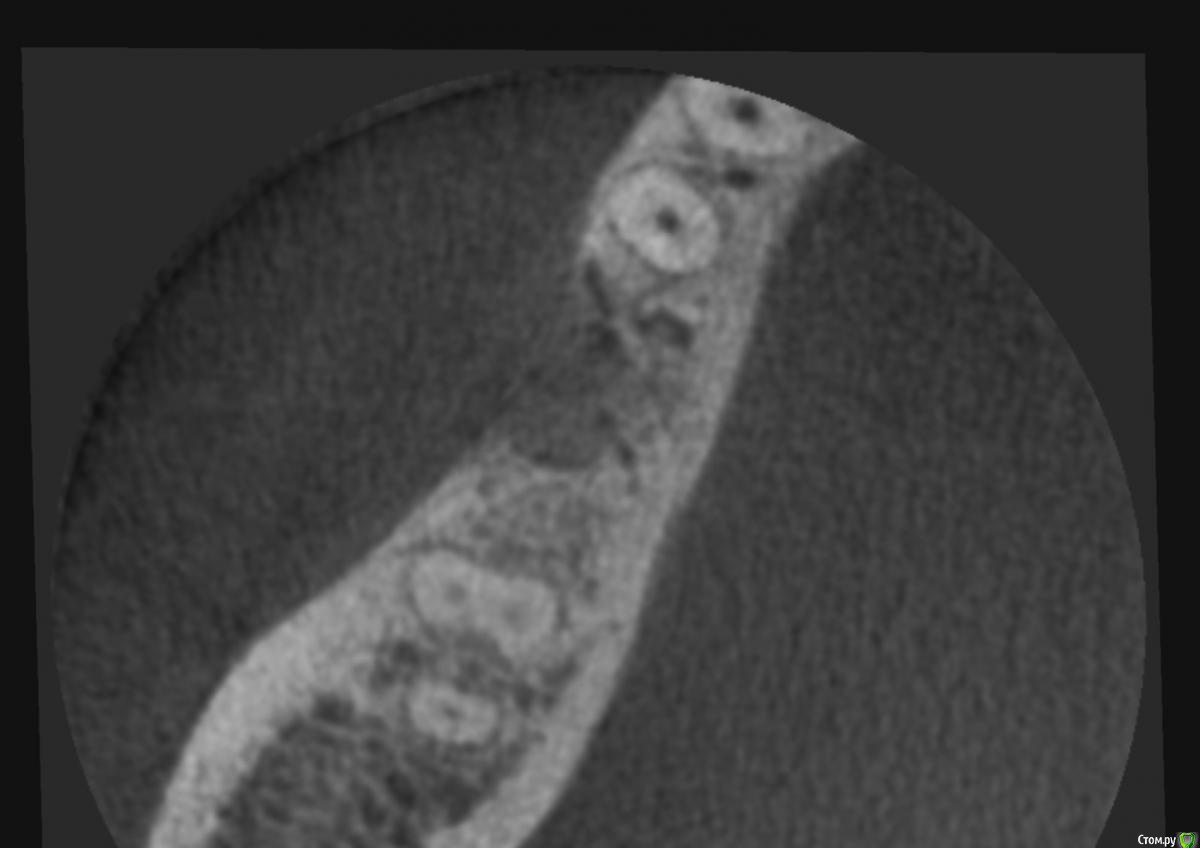

Irouil Опубликовано 20 июня, 2019 Поделиться Опубликовано 20 июня, 2019 одновременно?крутить чуть дистальнее или в ту же лунку?Одновременно Препарируйте туда, куда нужно, там апикально до канала достаточно твёрдых тканей чтобы стабилизировать. Естественно, все мягкое и непотребное выскрести. 3 Ссылка на комментарий

vgraev Опубликовано 21 июня, 2019 Поделиться Опубликовано 21 июня, 2019 если мягкотканные -кюретаж и жду? там же пятистеночный дефект будет - соответственно можно сразу ставить, позиционировать ,как посоветовал Irouil, правильно с точки зрения будущей ортопедической конструкции Ссылка на комментарий

Irouil Опубликовано 22 июня, 2019 Поделиться Опубликовано 22 июня, 2019 ИМХО там у Вас уже кость, расщепляйтесь над этим местом и мясом прикройте, будет круче чем в лучших домах Лондона Ссылка на комментарий